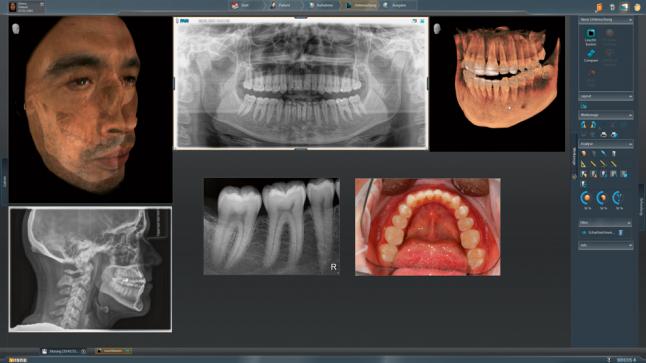

Модернизированный сенсорный экран Easypad с понятным и удобным интерфейсом позволяет выставить наилучшие параметры контрастности и разрешения. Систематизация данных по диагностике становится значительно удобнее и проще с ПО обработки изображений SIDEXIS 4, ORTHOPHOS.

1. Двух-и трёхмерные снимки совмещаются в одной программе

2. В одном окне можно сравнивать разные 3D-результаты

3. Считанные минуты уходят на просмотр анамнеза пациента.

Временная шкала Timeline – это мгновенное получение информации полного спектра проведённых обследований пациента в порядке хронологии. В результате – экономия рабочего времени и повышение качества работы в целом.

Интегрированная имплантология с GALILEOS Implant

Все манипуляции, связанные с операциями имплантологического плана эффективны и безопасны. Для того чтобы наиболее оптимальным способом спланировать лечение, есть возможность совмещения цифровых слепков и рентгеновских изображений и объединения данных SIDEXIS 4 и CEREC 44.